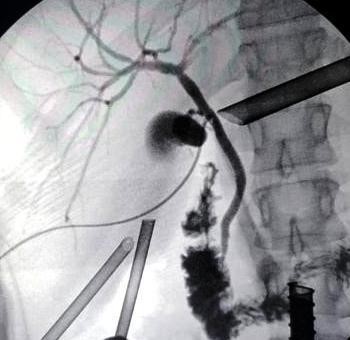

Colangiografía percutánea bajo visión directa con set para colangiografía laparoscópica con técnica de Seldinger introduciendo catéter plástico por cístico de vesícula patológica, identificando en vía biliar proximal o craneal al cístico cateterizado, el otro conducto cístico y la segunda vesícula biliar (sana) (ver imagen 6); el contraste no rellena la vesícula patológica, por lo que no existe comunicación entre ambos cuerpos vesiculares.

Imagen 6: Colangiografía que evidencia la presencia de conducto cístico y cuerpo vesicular de vesícula sana. No se evidencia comunicación entre ambos cuerpos vesiculares.